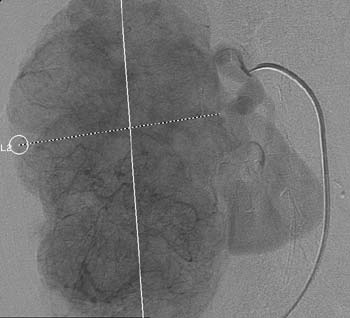

Рис. 5. Рак правой почки. Т3аN0M0. Гиперваскулярная опухоль V типа вакуля-ризации (измерительные линии) бугристой формы за счёт крупноузлового строения. Мелкие опухолевые сосуды равномерно распределены по площади опухоли.